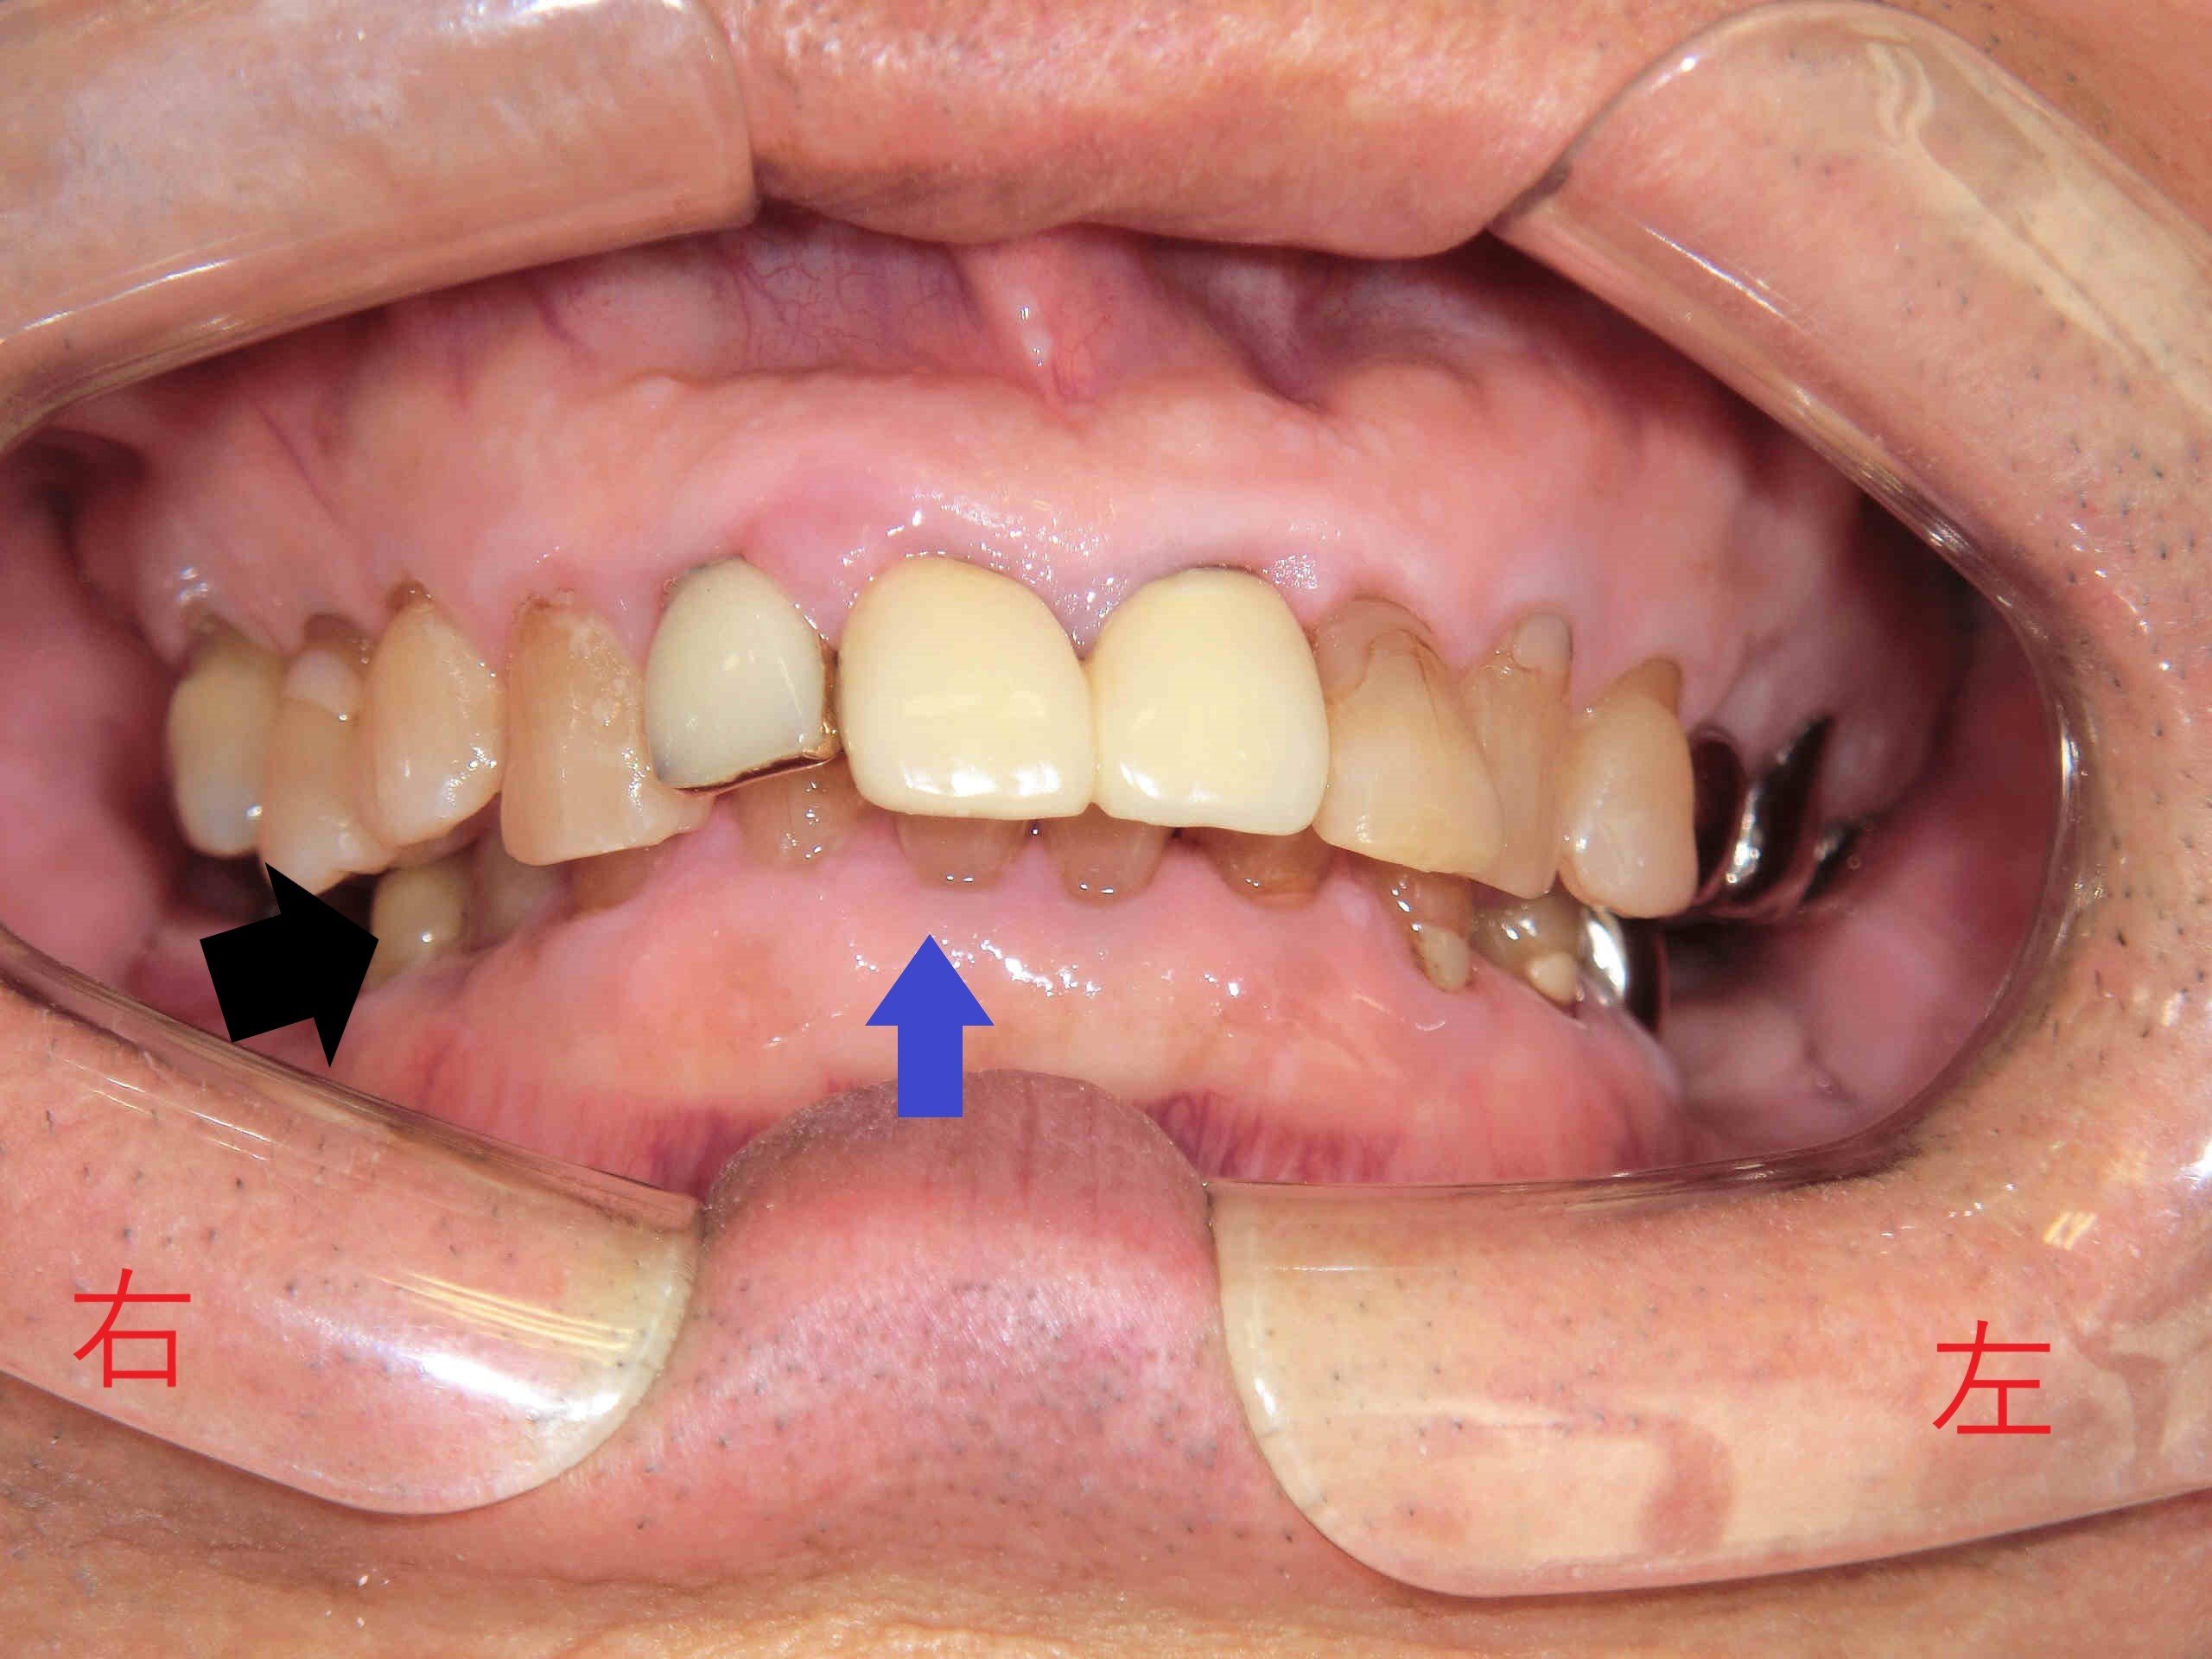

兵庫県三木市にお住まいの70代男性の患者様が、右下の被せ(黒色矢印)がグラグラして噛めないというお悩みで、〈みらい歯科クリニック〉に来院されました。なお、写真の掲載につきましては患者様の同意をいただいております。

また、患者様は“上顎前歯の出っ歯”を非常に気にしておられたため、丁寧にご説明したうえで、全顎的な治療計画を立案し、ご納得のうえで治療を開始させていただきました。写真で特に注目していただきたいのが、下顎前歯(青色矢印)です。

奥歯で噛んだ際に、下顎前歯が上顎前歯に隠れてほとんど見えなくなっている“深い噛み合わせ”の状態が確認できます。